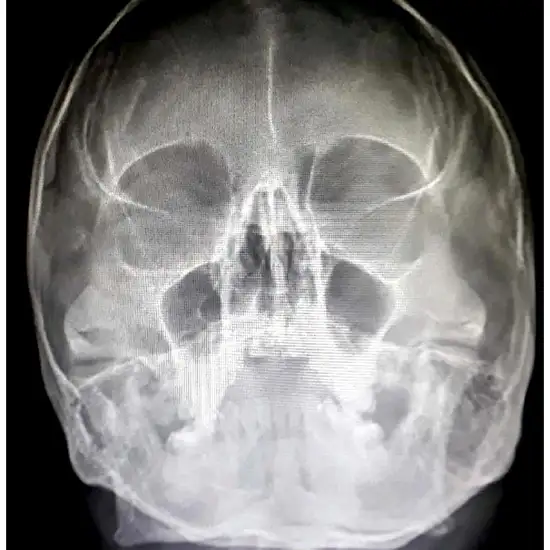

What is an X-ray PNS Test?

A PNS sinus x-ray can help doctors figure out what's wrong with the sinuses. Sinuses are cavities in the bones of the skull that are filled with air and lined with mucous membranes.